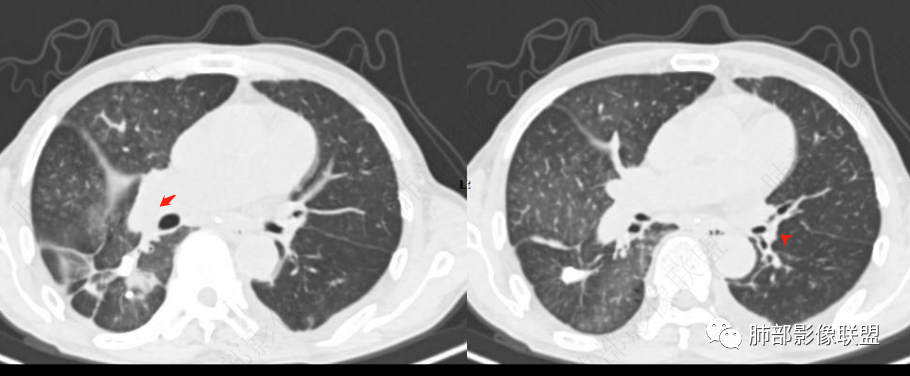

这些区域肺动脉增粗明显,围绕肺动脉周围GGO,但是局部小叶间隔不增厚,按理应该考虑肺动脉高压所致肺部改变

单肺的腺泡结节,一般吸入性,肺泡出血,追问临床有无咯血,血红蛋白血色素等指标,这么看来结合肺动脉高压,肺水肿,反晕病灶,二聚体,重点考虑肺栓塞。

周围区域连续些看,感觉有树芽征。

如果这个树芽征明确的话,这个就不是肺水肿。可以做个最大密度投影或多方位观察再次确定是否有树芽征。弥漫性中轴间质和周围间质增厚常规就两个疾病谱,癌淋或肺水肿。而且这个人有明确的右肺明显。结合可疑树芽征,很多可以看到沿着肺动脉走形的磨玻璃影,需要可疑血源播散性转移或血管源性恶性肿瘤病变,再就是嗜血管的淋巴源性的恶性肿瘤。血管肉瘤,血管内淋巴瘤病可以这个表现,之前还碰见过一个,好像是NK/T淋巴瘤也这个表现,这个有点记不清了。

明显反网格征。中心的GGO,所以这是以肺动脉为主的病变。不是静脉的

2.右肺广泛密度增高、腺泡结节样磨玻璃影,血管影明显扩张,小叶间隔增厚。

(5)可合并肺梗死,表现为肺外周胸膜下密度均匀的楔形病灶,尖端指向肺门。可出现反晕征及空洞等。